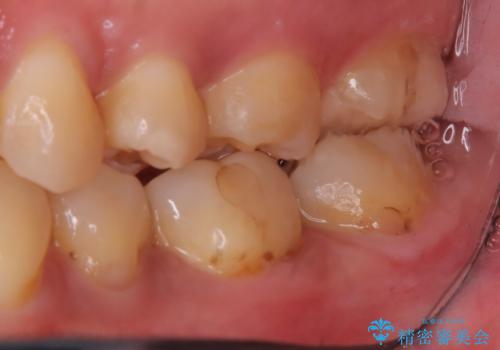

- 主訴:左上の銀の詰め物、笑うと見えそうで気になるので白くしたい。

保険適応のメタルインレーが入っていたため、適合性・審美性の良いセラミックインレーでのやり替えとなりました。

保険適用のメタルインレーを除去したところ、歯質との境目部分にカリエスを認めたため、カリエス除去しCR裏層の後、セラミックインレーを形成しました。